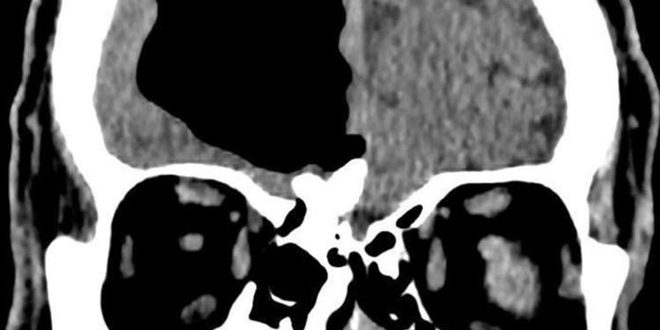

وذكر موقع روسيا اليوم أن الأطباء اكتشفوا وجود “تجويف هوائي” يبلغ طوله 10 سنتيمترات في النصف الأيمن من دماغ رجل مسن نقل إلى المستشفى عقب شعوره بالدوار وسقوطه على الأرض بعد أن تبددت شكوكهم بإصابته بسكتة دماغية.

وبينت نتائج التصوير بالرنين المغناطيسي لدماغ الرجل المسن وجود ما يسمى بالفتق الهوائي وهو ما يلاحظ عادة لدى المرضى الذين يعانون من إصابات في أجزاء معيّنة من الجسم والأعضاء الداخلية.

كما كشف الفحص وجود ورم عظمي (تشكّل حميد في عظام الوجه يفصل بين تجويف الأنف والدماغ)، دخل من خلاله الهواء إلى دماغ الرجل وبقي فيه لعقود من الزمن، ما أدى إلى الضغط على الدماغ وتعطيل التنسيق في بعض وظائفه الحيوية وهذا ما أدى إلى شكوى الرجل من الدوار المتكرر.